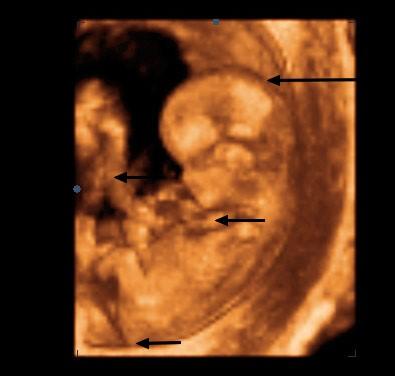

Trojrozměrné znázornění plodu starého asi 10-11 týdnů. I když je mozková část hlavy ještě poměrně velká, rýsuje se pod vypouklým čelem jemný obličej s vyvýšeným nosíkem a malými ústy. V oblasti zad je dobře patrná páteř složená z jednotlivých obratlů. Šipkami shora dolů označeny: temeno, pupečník, levá paže, kostrč.